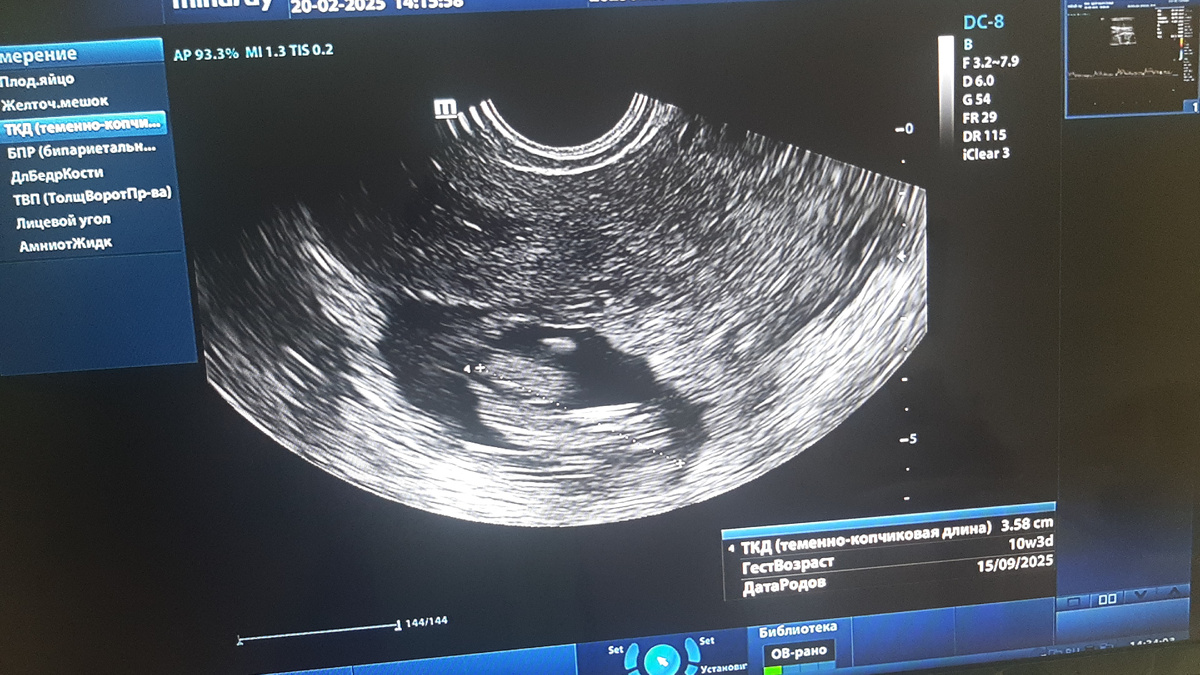

У правого ребра матки лоцируется эктопическое плодовместилище ( см иллюстрационную сканограмму) .

В ПЯ лоцируется живой эмбрион , по КТР на 10 недель 3 дня, отчётливо определяется сердцебиение плода 136 уд в минуту.

Эктопию расцениваю, как трубную.

Хотя несколько смущает возраст эмбриона ( в классическом варианте подобная эктопия прерывается в 7- 8 недель) и слишком большой диаметр трубы- чисто визуально.